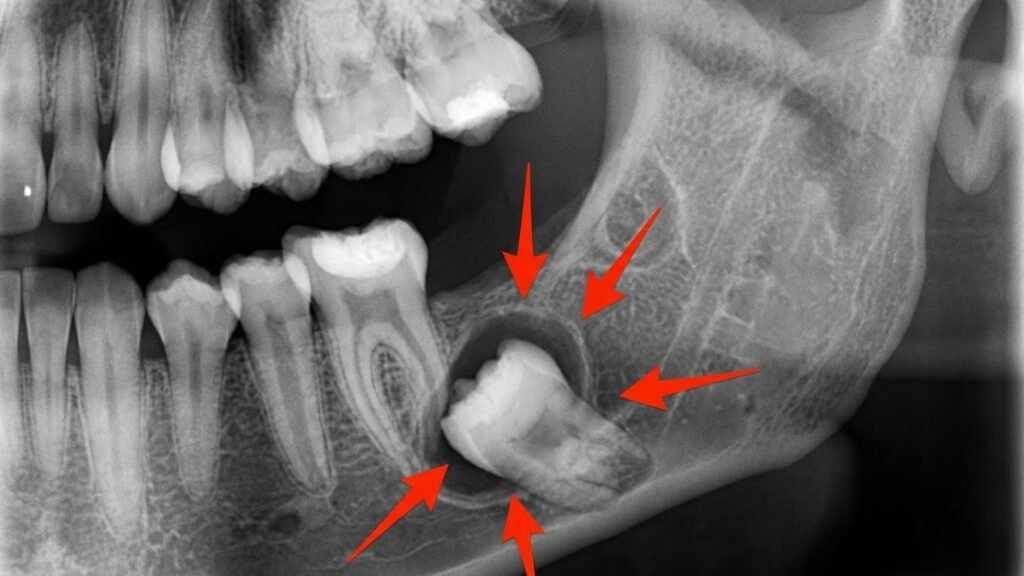

- Solicitar radiografias: Geralmente uma radiografia panorâmica ou tomografia computadorizada para visualizar a posição exata dos sisos e sua relação com estruturas importantes (nervos, seios maxilares)

- Radiografia panorâmica: Mostra todos os dentes e estruturas ósseas em uma única imagem

- Tomografia computadorizada: Fornece imagens tridimensionais, especialmente útil para casos complexos

- Radiografias periapicais: Imagens detalhadas de dentes específicos